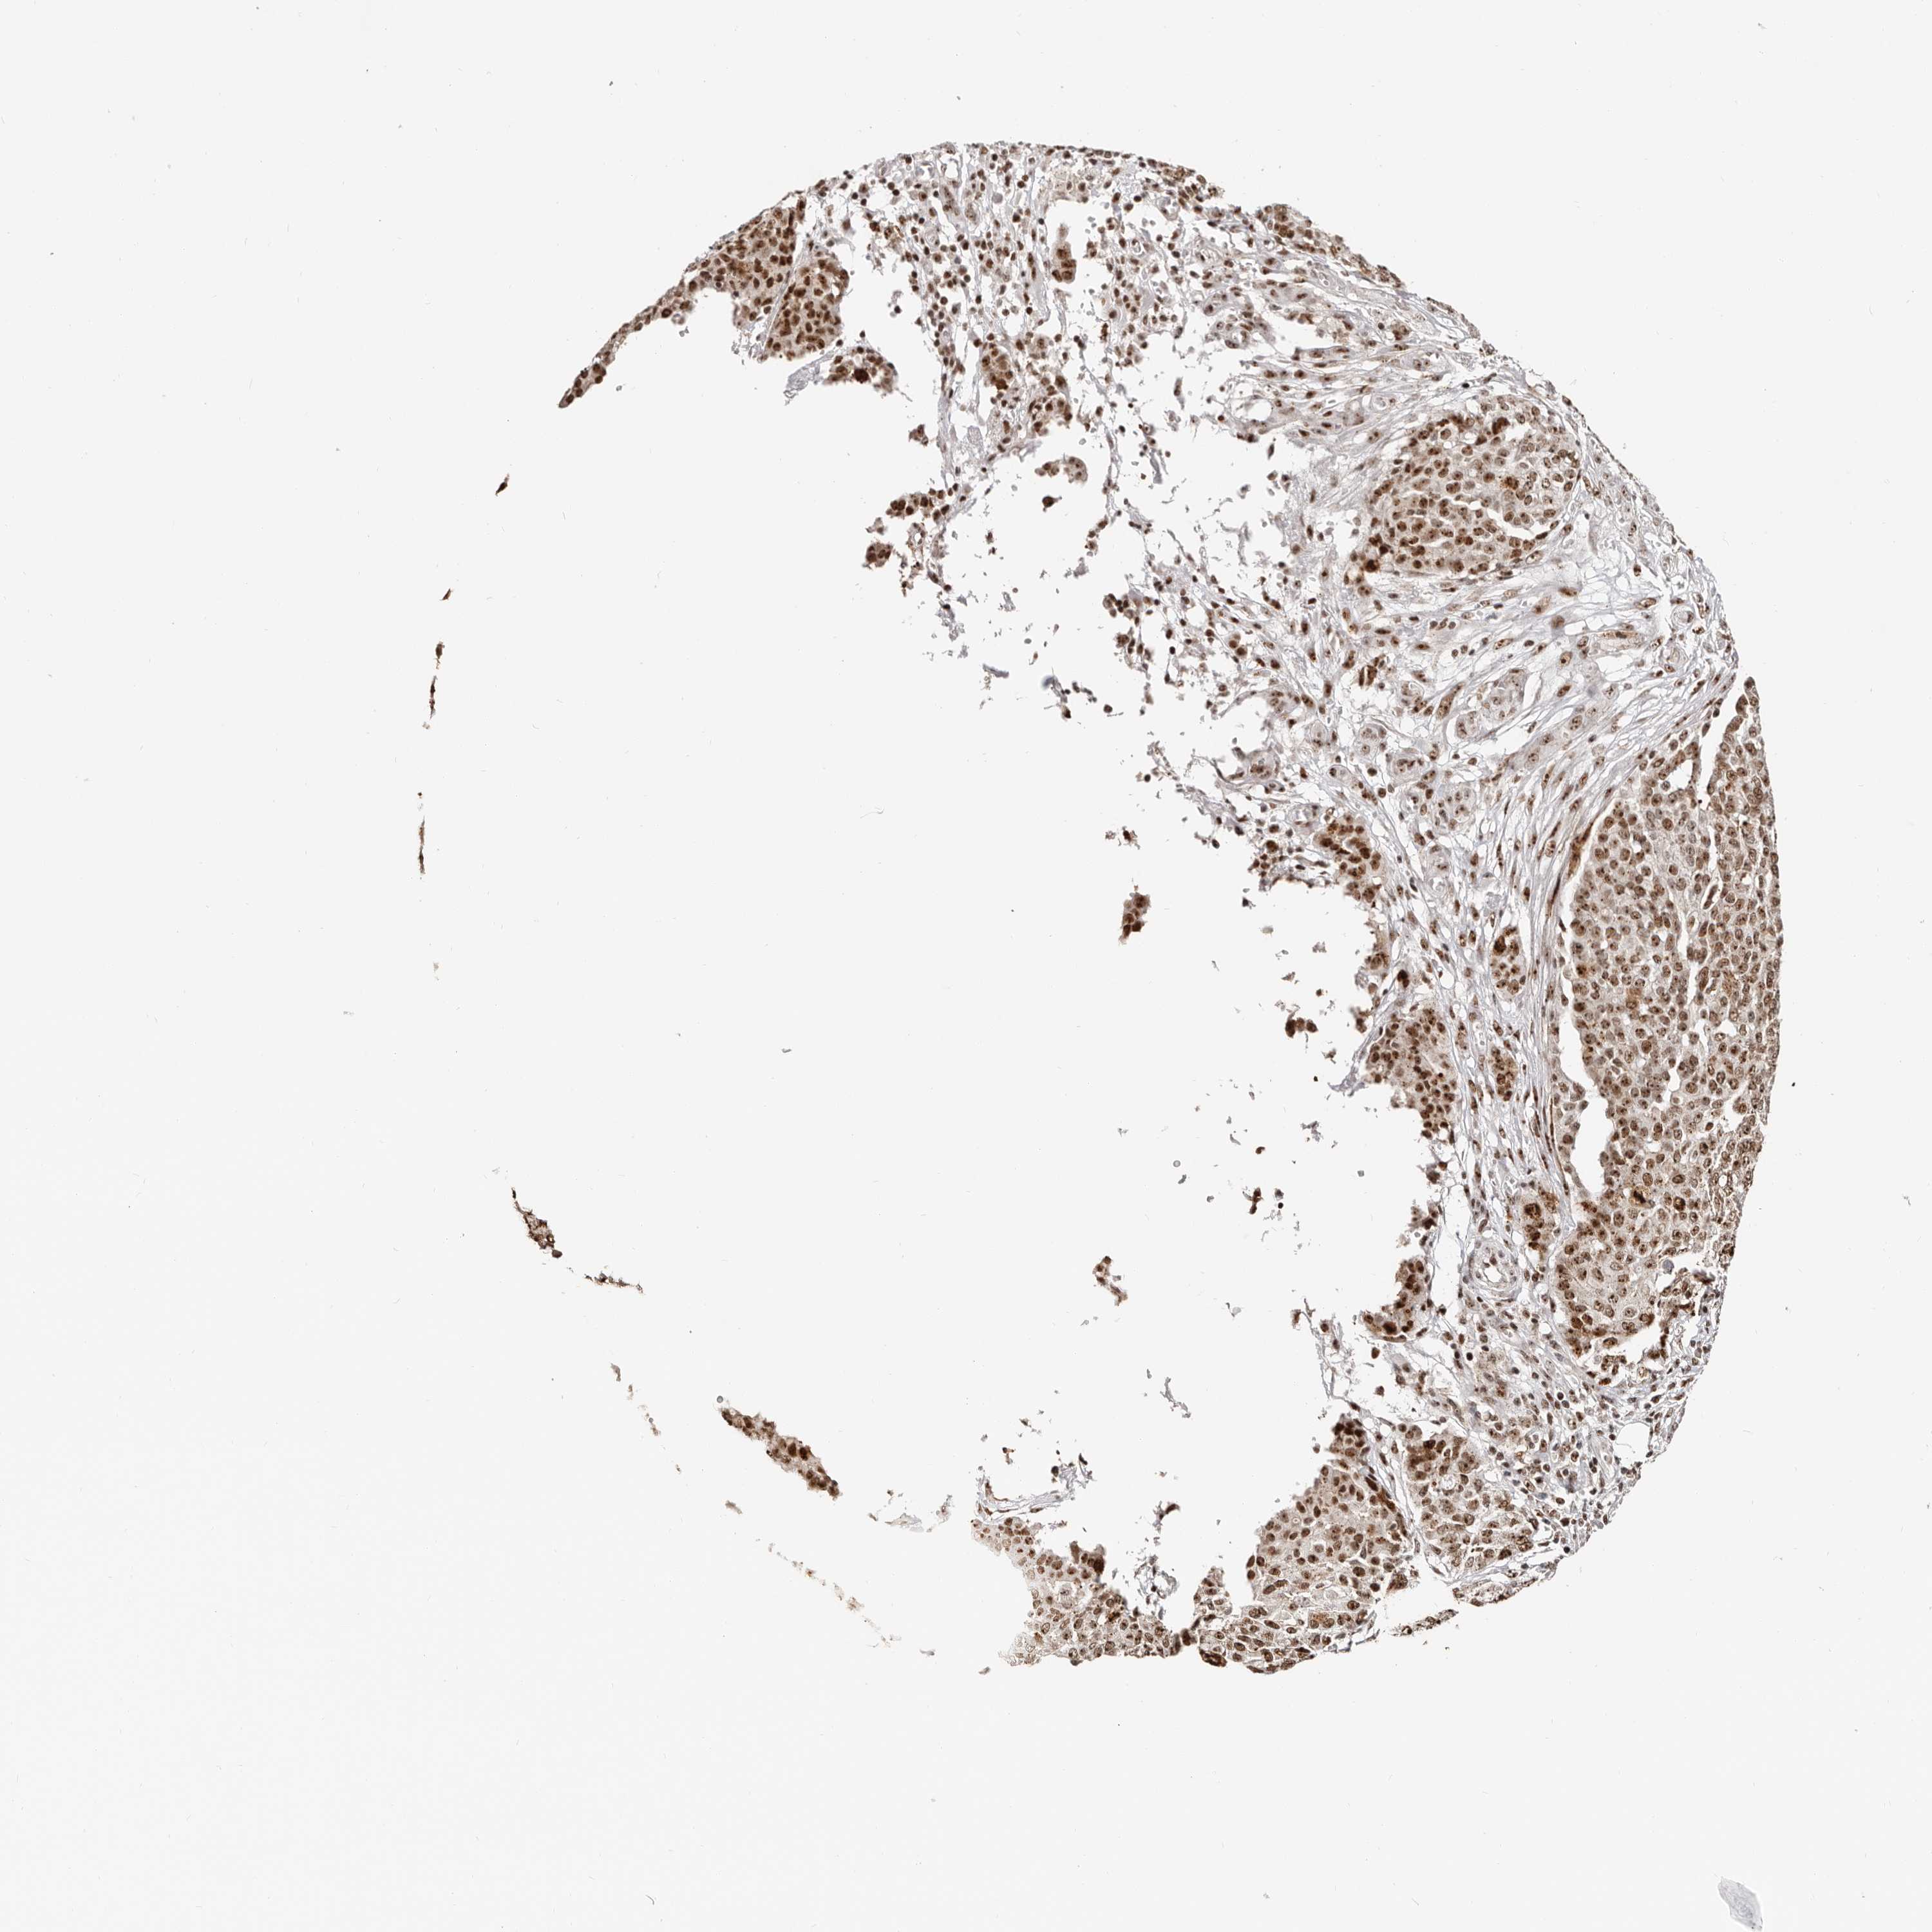

OVARIAN CANCER - Protein expressioni

A mouse-over function shows sample information and annotation data. Click on an image to view it in a full screen mode. Samples can be filtered based on level of antibody staining by selecting one or several of the following categories: high, medium, low and not detected. The assay and annotation is described here.

Note that samples used for immunohistochemistry by the Human Protein Atlas do not correspond to samples in the TCGA dataset.

Antibody stainingi

Antibody staining in the annotated cell types in the current human tissue is reported as not detected, low, medium, or high, based on conventional immunohistochemistry profiling in selected tissues. This score is based on the combination of the staining intensity and fraction of stained cells.

Each image is clickable and will lead to virtual microscopy that enables deeper exploration of all samples and also displays staining intensity scores, fraction scores and subcellular localization as well as patient and tissue information for each sample.

Antibody HPA030142

Antibody HPA030143

Cystadenocarcinoma, serous, NOS

Carcinoma, endometroid

Cystadenocarcinoma, mucinous, NOS

Carcinoma, NOS